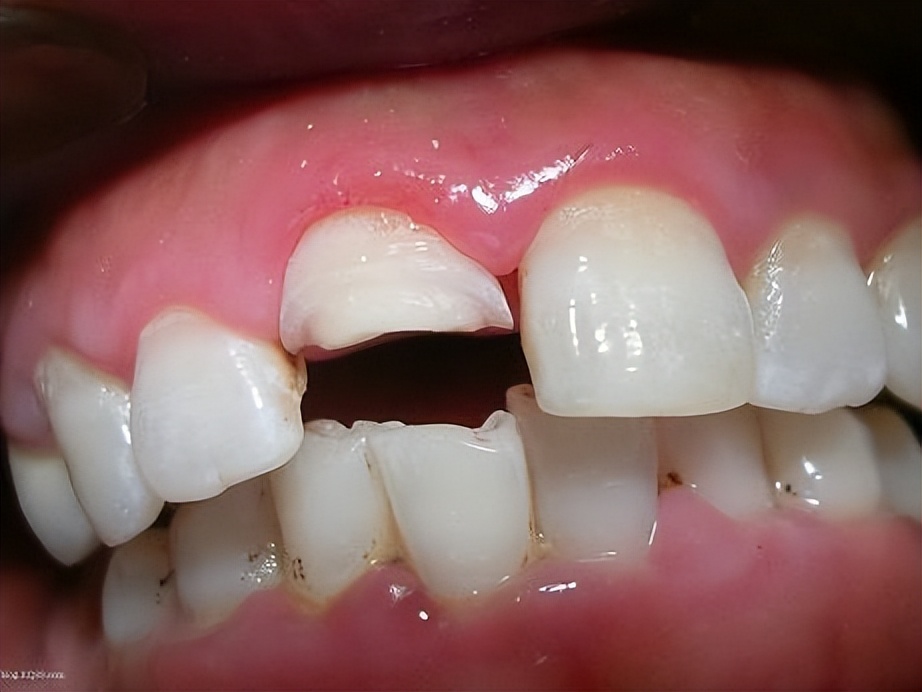

上图是一个十六岁的男孩,剧烈运动后摔倒,然后把上门牙磕断了,如果我们遇到外伤,把门牙磕断了,应该怎么办呢?你且往下看,让我详细说给你听。

如果前牙外伤,单纯的牙冠缺损,牙根没有问题,大致情况如下图

只损伤切角,未伤及牙根和牙髓。